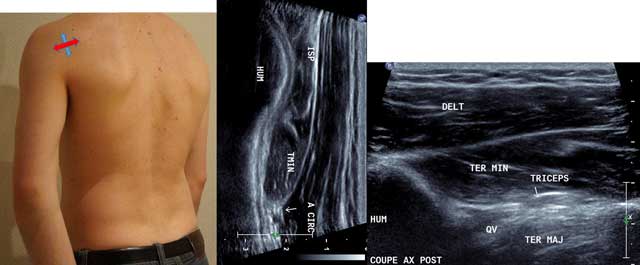

Figure 3

Sagittal oblique view (blue arrow) and axial intermediate view (red arrow) with HUM: Humerus, ISP: Infraspinatus, TMIN: Teres minor, A CIRC: Axillar Artery, DELT: Deltoid Muscle, TER MAJ: Teres Major, QV: Velpeau space, Triceps: Tricipal Muscle.